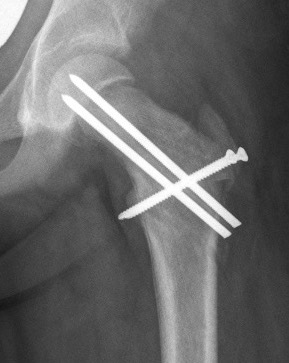

Base of neck / Kramer

Technique

- closing wedge anterior and superior

Disadvantage

- risk AVN

- shortens neck further - worsens LLD